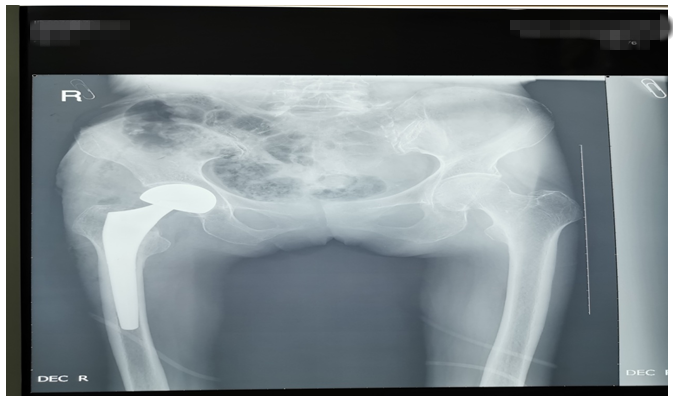

還有一位76歲鄧大媽,外傷致右側(cè)股骨頸骨折。外傷后因疫情鄧大媽一直未就診,在家非常痛苦,因疼痛不能平臥,一直坐位,臀部褥瘡形成,同時被骨折疼痛折磨地夜不能睡、不思飲食。鄧大媽基礎(chǔ)病較多,有高血壓病、腦梗塞、心臟病等病史,因骨折后時間長、錯位明顯,入院后積極治療內(nèi)科疾病,完善各項輔助檢查,在麻醉師及內(nèi)科醫(yī)師協(xié)助下,為鄧大媽成功行右側(cè)髖置換術(shù),手術(shù)順利。術(shù)后鄧大媽的臉上又有了笑容,夜間也能休息好了,術(shù)后第二天就開始下床活動,家屬看到自己的老母親恢復地這么好,非常滿意。(見下圖)

右髖正側(cè)位手術(shù)前后對比圖